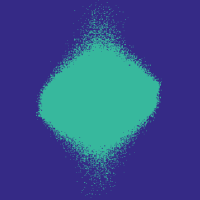

Figure 7 illustrates the best-performing randomized indices vs. our learned set of indices in the -space along the and directions. When optimized for the linear decoder, the indices of [3, 4] concentrate on low frequencies. While our strategies based on optimizing and (again using ) also do this to some extent, there is a stark contrast in the shape, since we do not restrict ourselves to patterns exhibiting circular symmetry.

Table III illustrates the overall test performance of each approach, in addition to the error obtained by the best adaptive (i.e., image dependent) -sample approximations with respect to the -space basis. Based on these numbers, the learning-based approach slightly outperforms the randomized variable-density based approach of Roman et al. [4], which in turn slightly outperforms that of Lustig et al. [3]. The best PSNR in each case is achieved by the indices corresponding to ; with this choice, even the linear decoder leads to an improvement over [3] and [4] used with BP, while using our indices alongside BP provides a further improvement. Finally, based on Figure 8, it appears that the improvement of our indices is actually more significant in the relevant parts of the image where the knee is observed, with finer details being seen at and sampling rates.